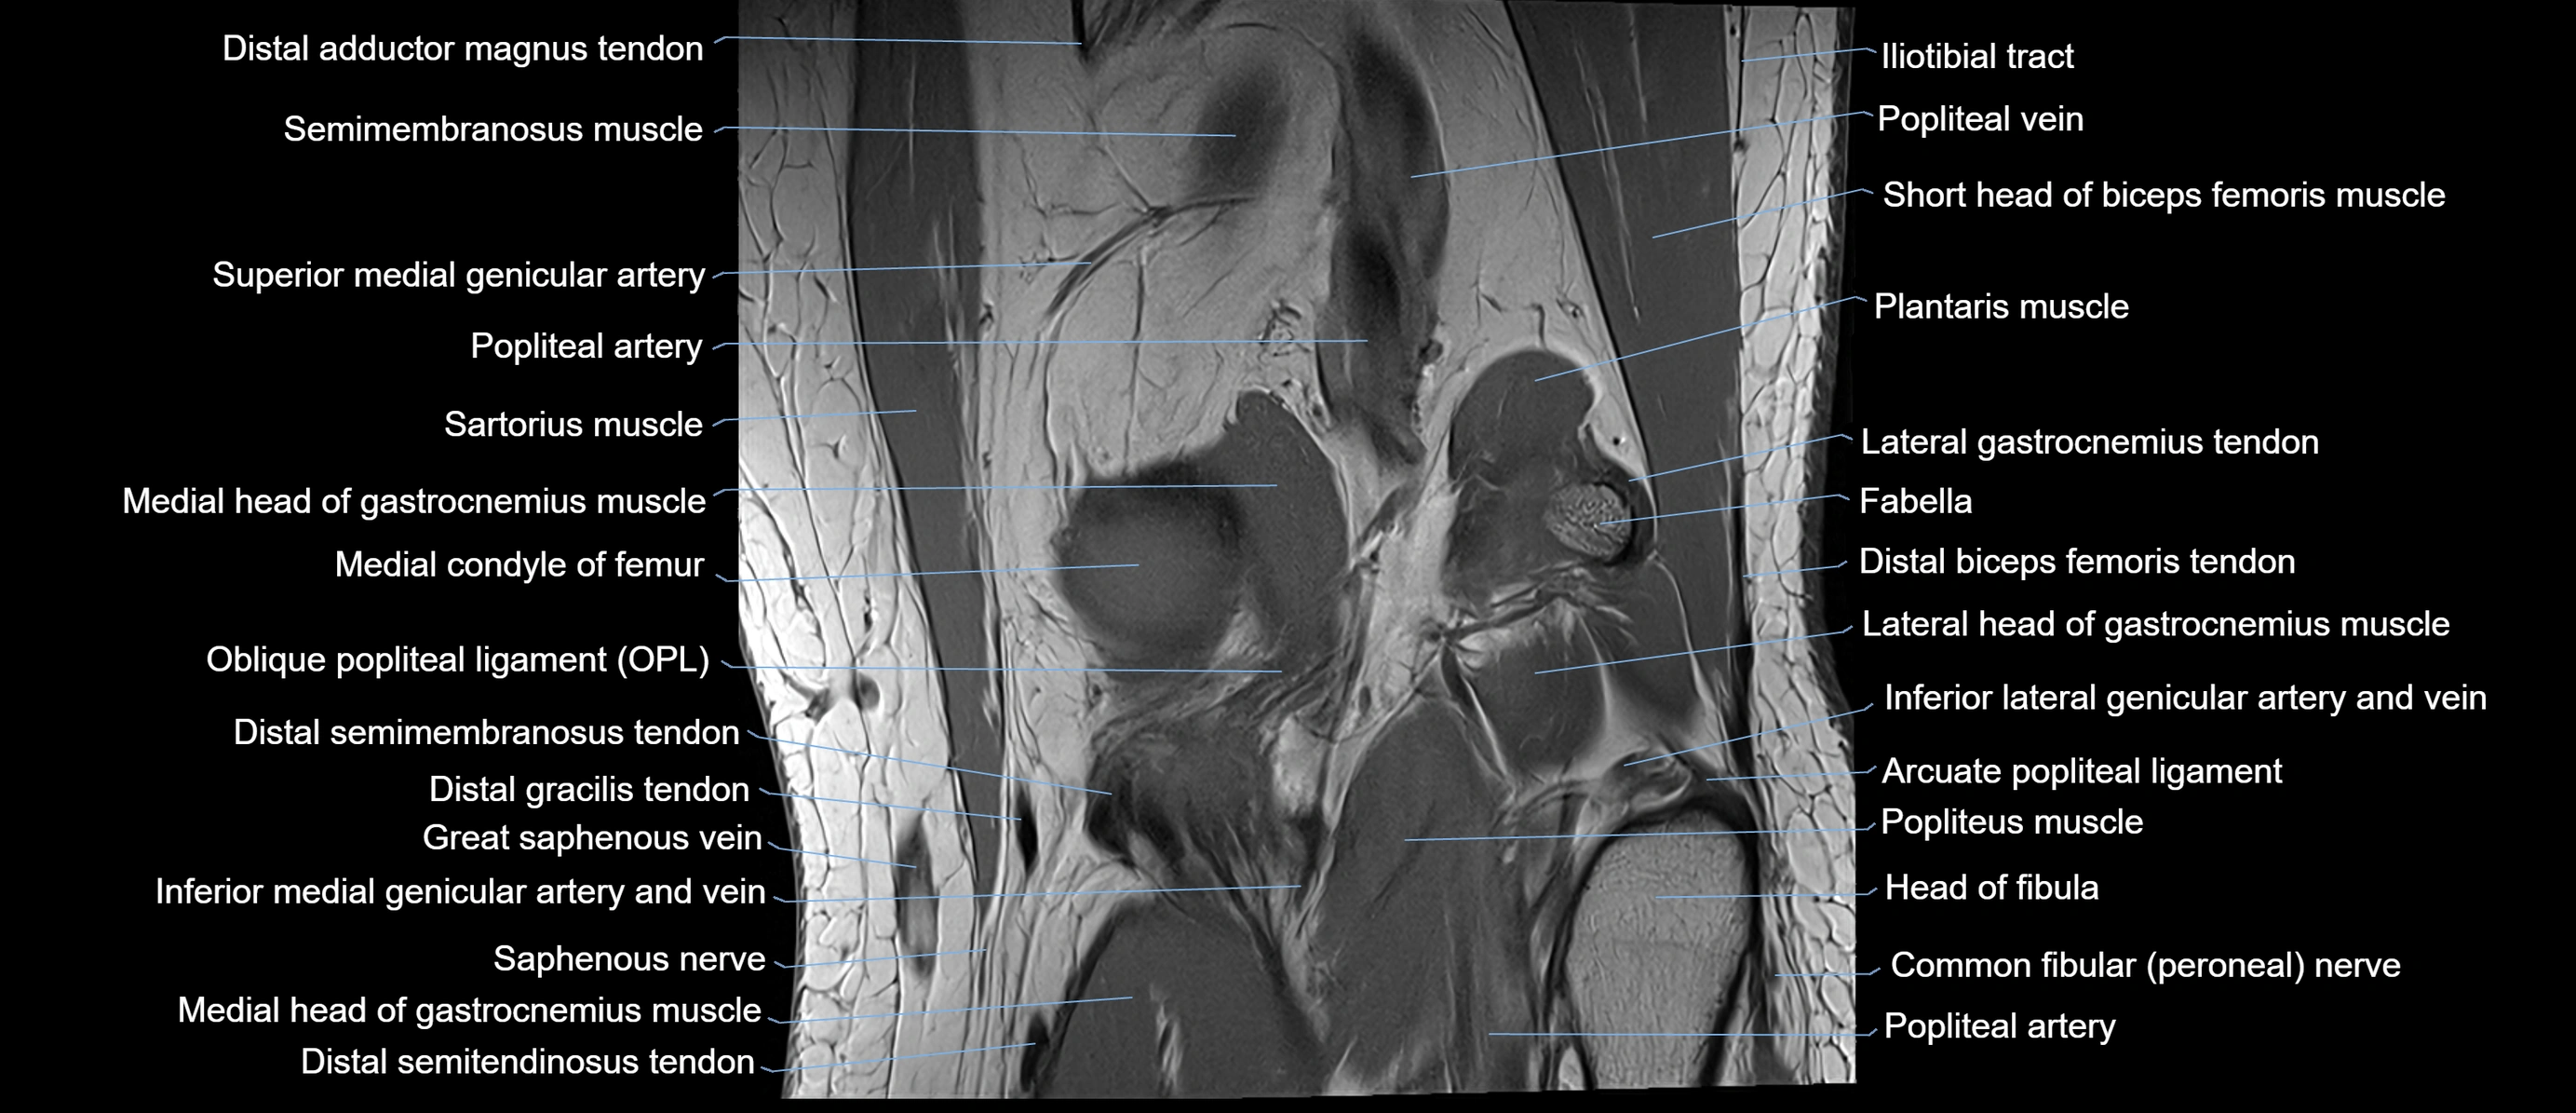

- Oblique popliteal ligament

- Popliteal artery

- Popliteal vein

- Popliteus muscle

- Semimembranosus muscle

- Arcuate popliteal ligament

- Distal biceps femoris tendon

- Distal semimembranosus tendon

- Head of fibula

- Lateral head of gastrocnemius muscle